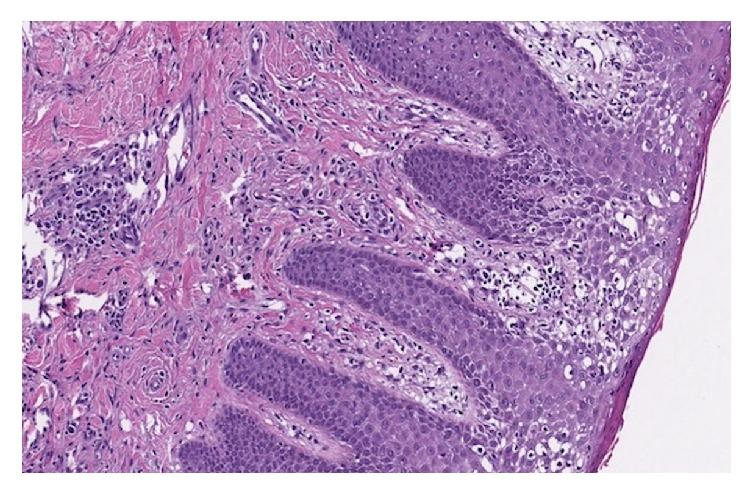

Mycosis Fungoides Involving the Dorsal Tongue.

Mycosis fungoides (MF) is a rare cutaneous T-cell lymphoma (CTCL) which can cause significant morbidity. During the disease course, it classically will progress through three clinical stages in the skin: patch-, plaque-, and tumor-stage. The early stages exhibit various histopathological mimics that often lead to misdiagnosis. It rarely affects the oral cavity. Oral MF is historically associated with poor prognosis. We present a rare case of MF afflicting the dorsal tongue and extremities of a 72-year-old male.